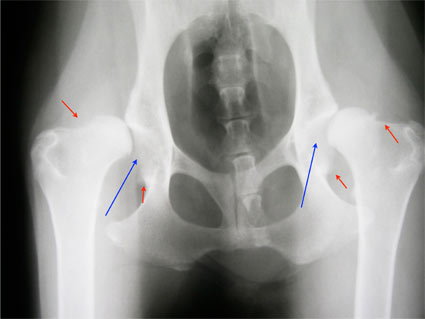

A csípőízületi diszplázia lényege hogy a csípőízületet alkotó combcsontfej nem megfelelően illeszkedik a medencecsont ízületi vápájába, ami az ízület részleges (esetleg teljes) ficamodásával jár.

Az állandóan ficamodó ízületben egy idő után porckopások jönnek létre a ki-be mozduló combcsontfej porca, és a medence vápájának pereme között. Mindemellett steril ízületi gyulladás, egy idő után porcdegeneráció, porcfelrakódások, degeneratív ízületi elváltozások, összefoglalva: csípőízületi arthrosis jön létre.